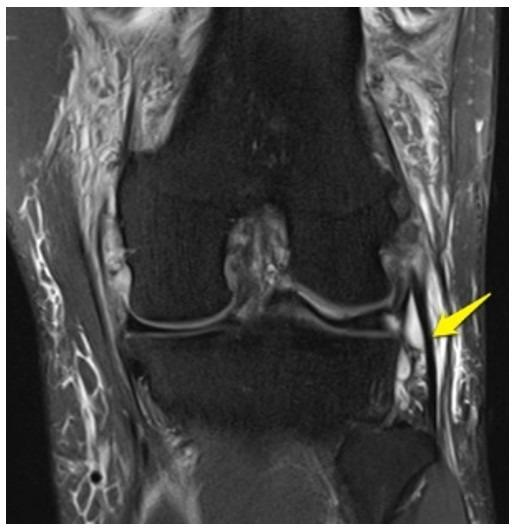

What imaging plane is this?

coronal

What anatomy is the arrow pointing to?

lateral collateral ligament

Medial meniscus

medial collateral ligament

posterior cruciate ligament

Which letter is pointing to the posterior cruciate ligament?

e

Which letter is pointing to the anterior cruciate ligament?

c

Which letter is pointing to the patellar ligament?

b